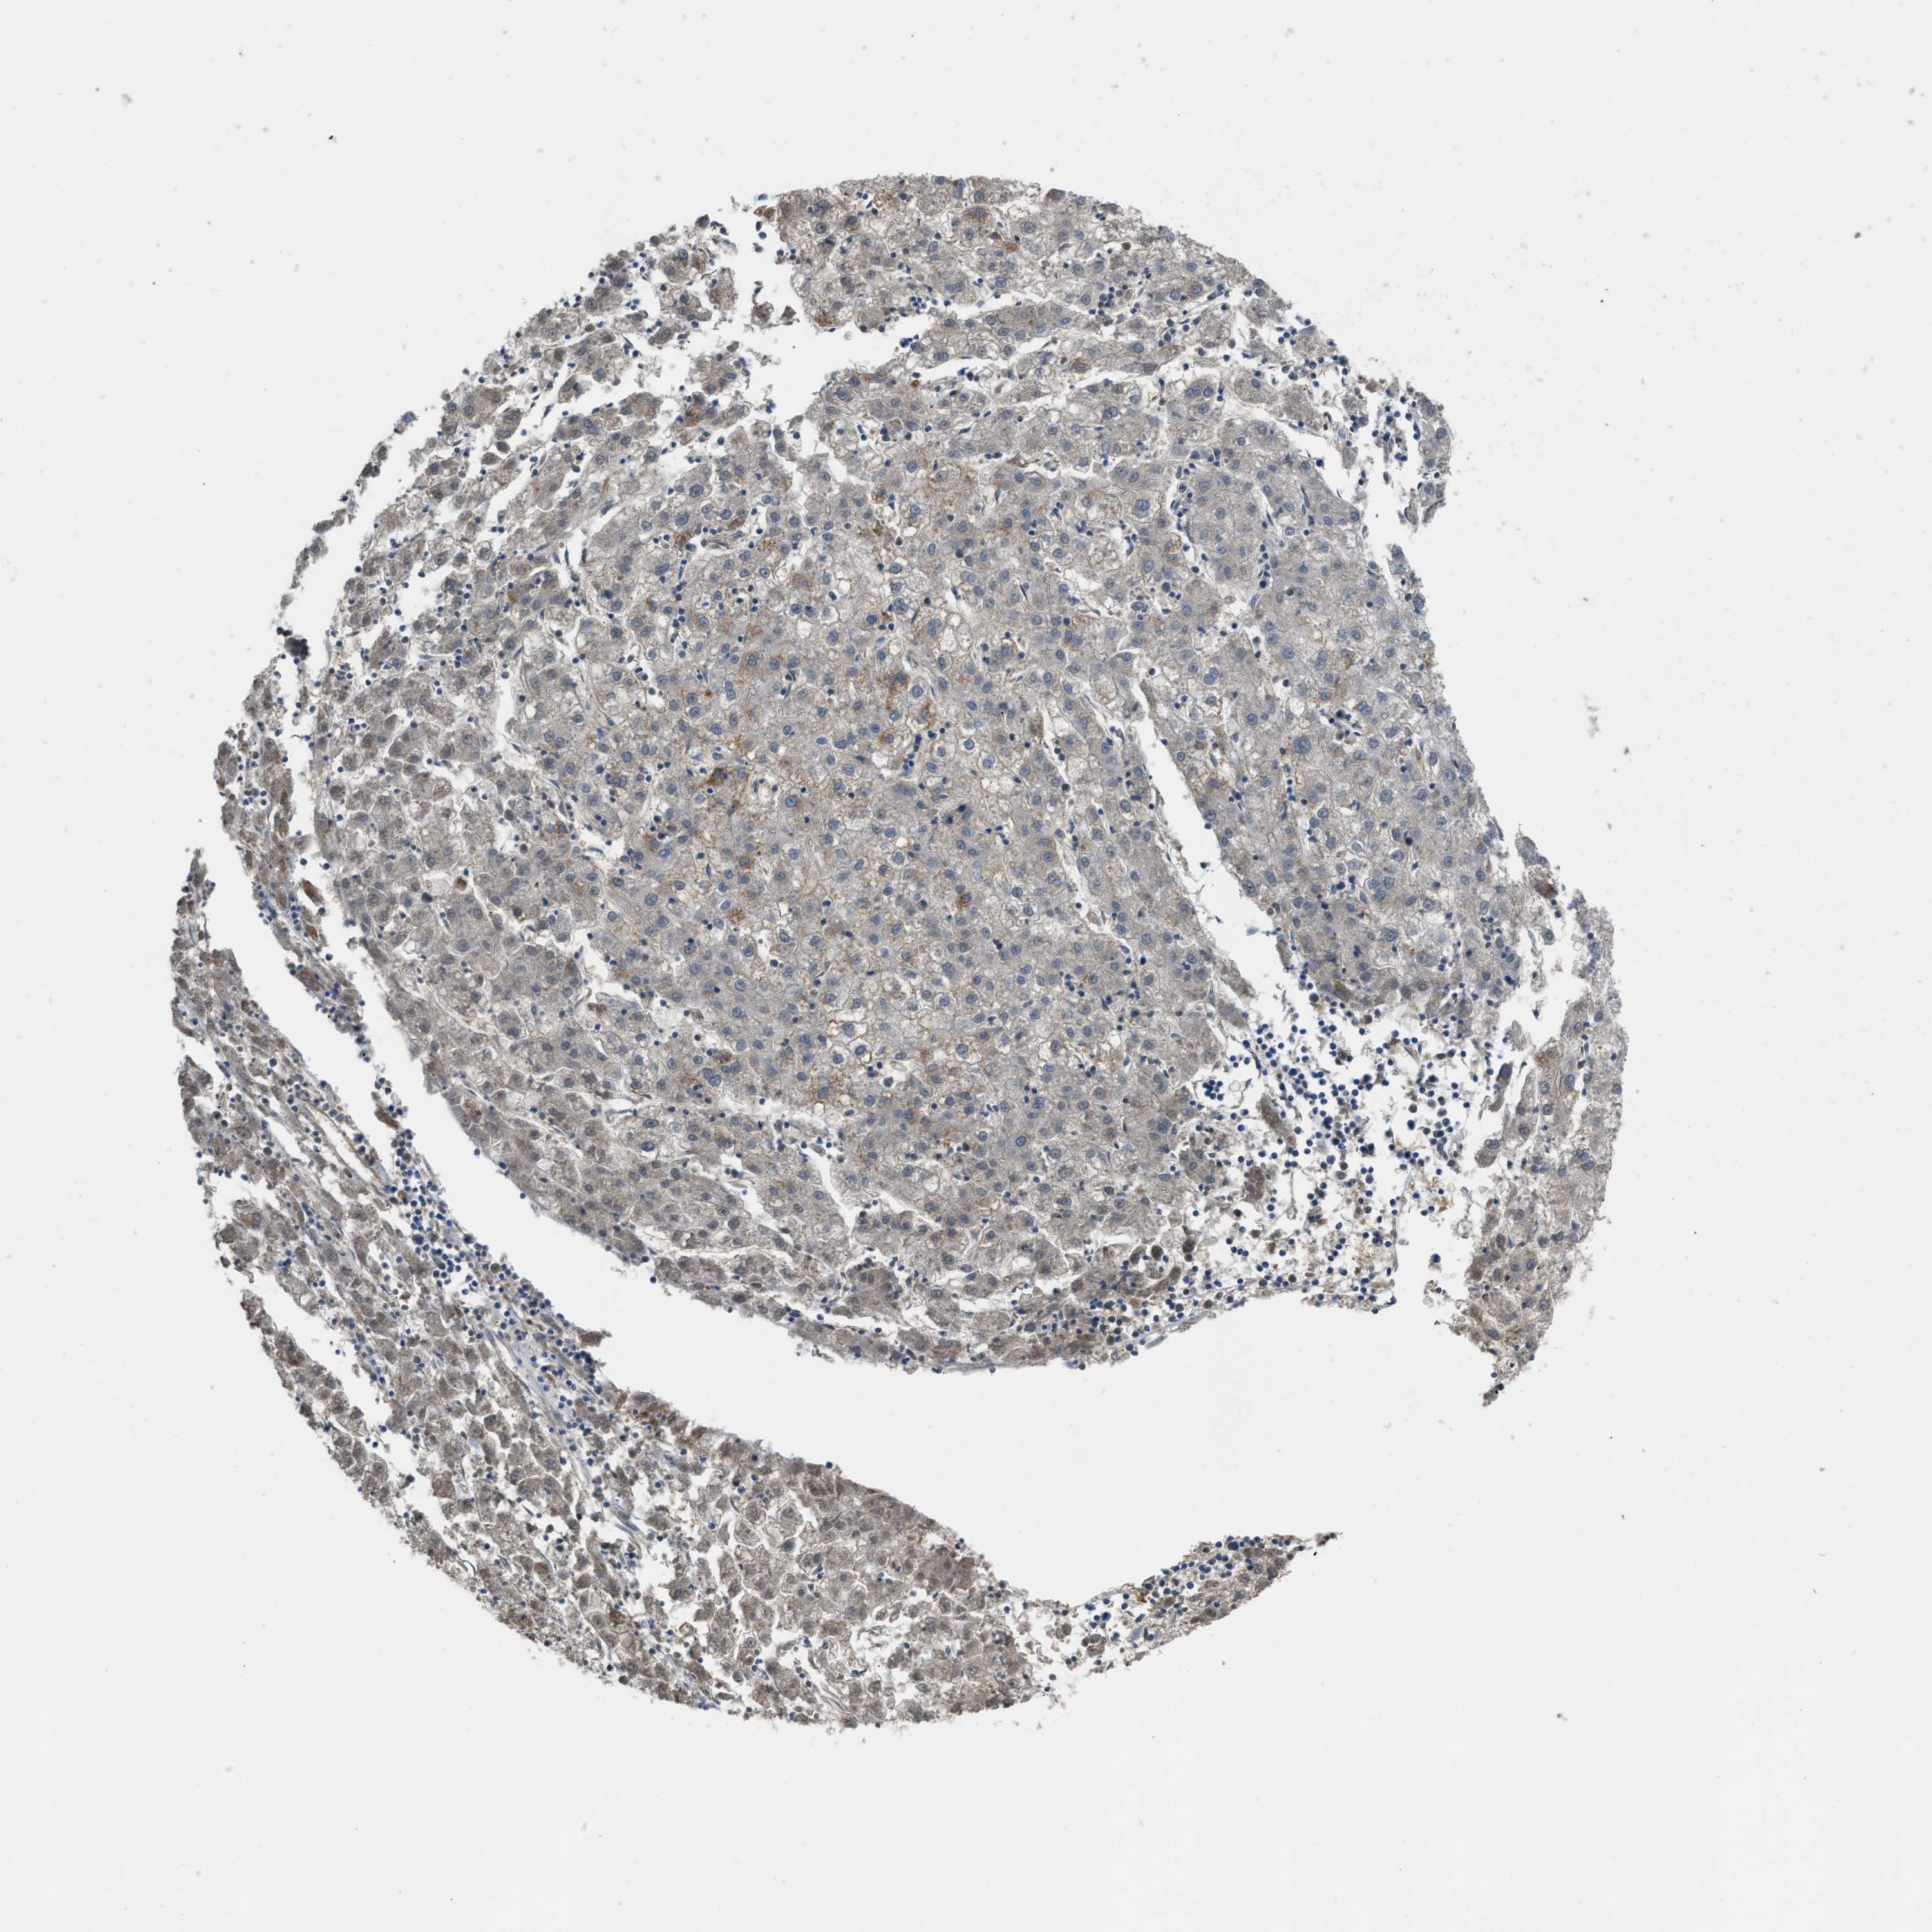

LIVER CANCER - Protein expressioni

A mouse-over function shows sample information and annotation data. Click on an image to view it in a full screen mode. Samples can be filtered based on level of antibody staining by selecting one or several of the following categories: high, medium, low and not detected. The assay and annotation is described here.

Note that samples used for immunohistochemistry by the Human Protein Atlas do not correspond to samples in the TCGA dataset.

Antibody stainingi

Antibody staining in the annotated cell types in the current human tissue is reported as not detected, low, medium, or high, based on conventional immunohistochemistry profiling in selected tissues. This score is based on the combination of the staining intensity and fraction of stained cells.

Each image is clickable and will lead to virtual microscopy that enables deeper exploration of all samples and also displays staining intensity scores, fraction scores and subcellular localization as well as patient and tissue information for each sample.

Antibody HPA018910

Antibody HPA018921

Antibody HPA018923

Staining

High

Medium

Low

Not detected

Intensity

Strong

Moderate

Weak

Negative

Quantity

>75%

75%-25%

<25%

None

Location

Nuclear

Cytoplasmic/membranous

Cytoplasmic/membranous,nuclear

Cholangiocarcinoma

Carcinoma, Hepatocellular, NOS